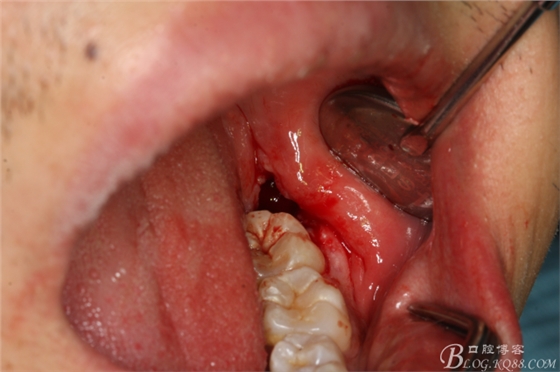

圖4.采用不切開、不翻瓣、利用暴露出來的牙冠進(jìn)行潛掘式分牙

圖5.高速渦輪鉆舌側(cè)潛掘法橫斷牙冠

圖6.舌側(cè)潛掘法完成

圖7.頰側(cè)潛掘法完成頰側(cè)牙冠橫斷